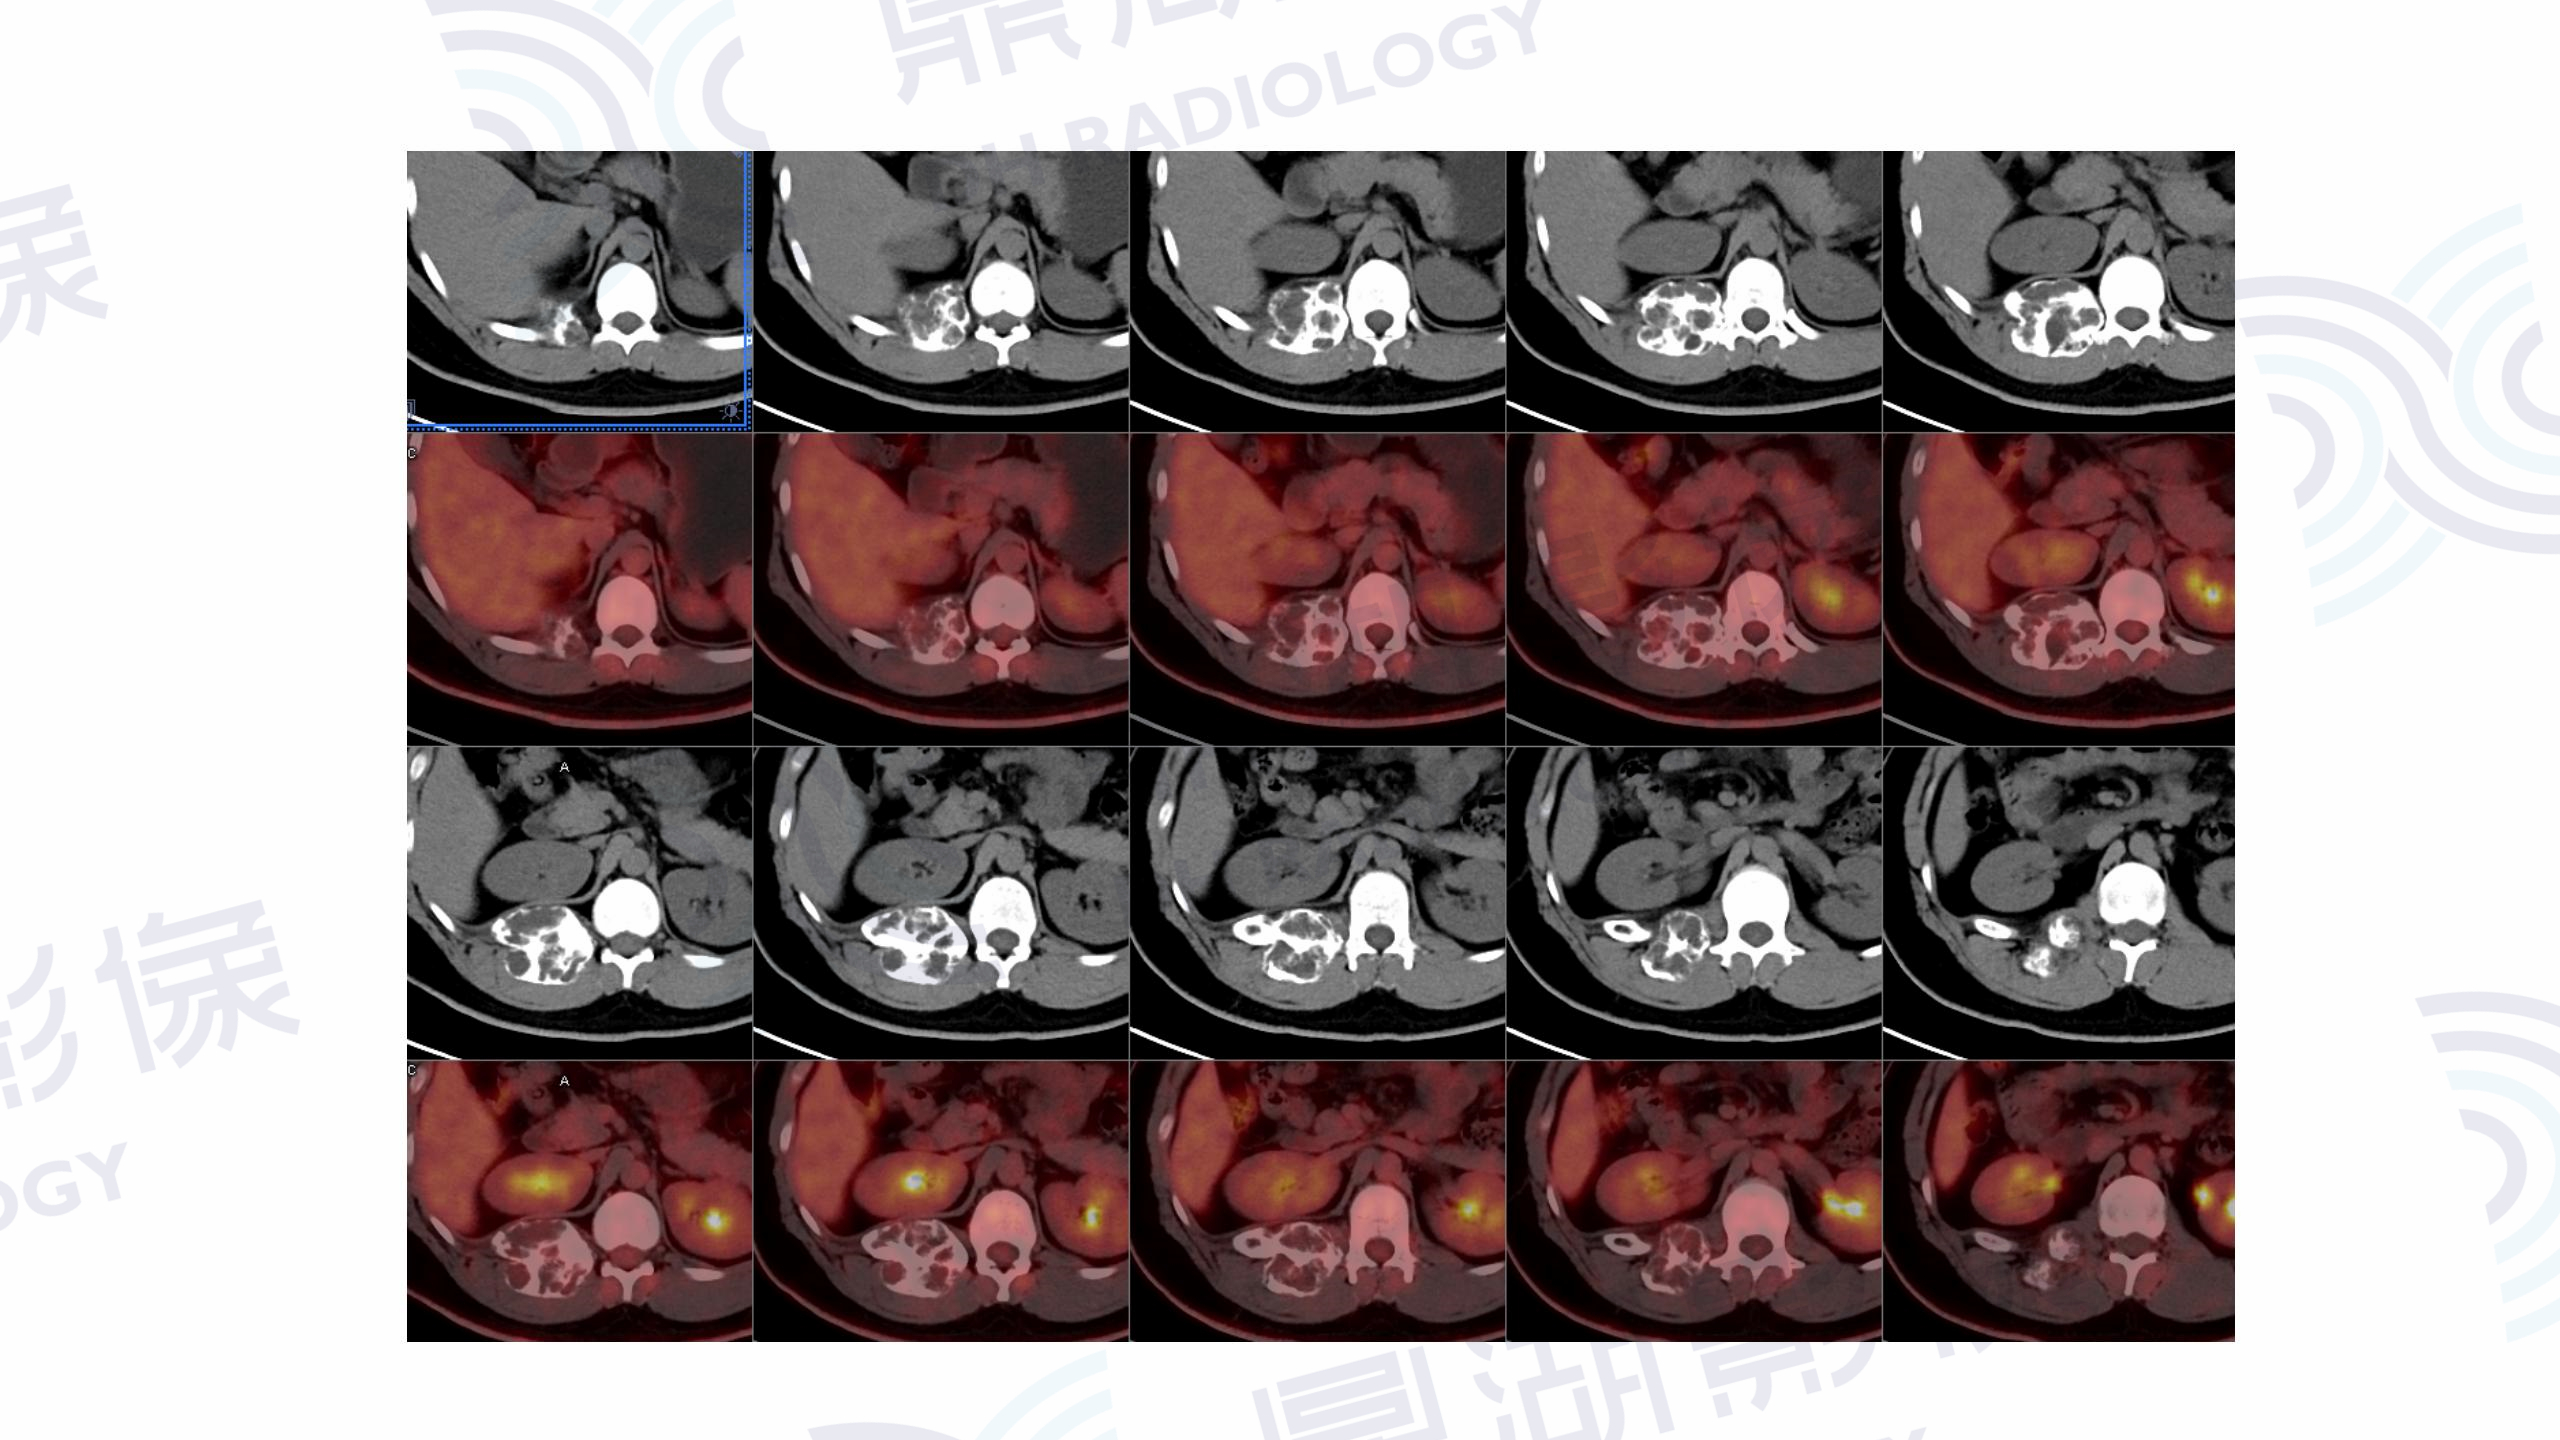

肋骨动脉瘤样骨囊肿

CT

PET

男  18岁

因摔跤到当地医院检查,发现右第12肋骨肿瘤样改变,怀疑肿瘤后进一步行PET/CT检查。